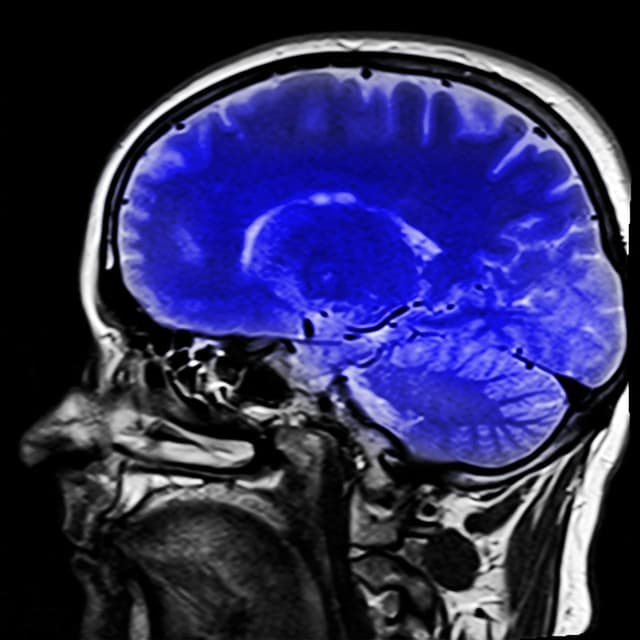

Des chercheurs français ont mis au point une technique qui pourrait révolutionner l’imagerie cérébrale médicale. Elle permet la visualisation des vaisseaux sanguins du cerveau à une échelle microscopique.

Une équipe de chercheurs du Laboratoire physique pour la médecine de Paris, affiliée à l’Inserm ainsi qu’à l’ESPCI Paris-PSL et au CNRS a expérimenté une nouvelle technique d’imagerie cérébrale médicale. Elle permet de visualiser la dynamique du flux sanguin cérébral à l’échelle microscopique. Cette technique est non invasive et repose sur l’utilisation d’ultrasons. Cette nouvelle technologie permettrait aux chercheurs et médecins d’observer le flux sanguin dans les vaisseaux du cerveau. Cela donnerait ainsi des informations sur la vitesse d’écoulement de ce flux, mais aussi sur sa direction.